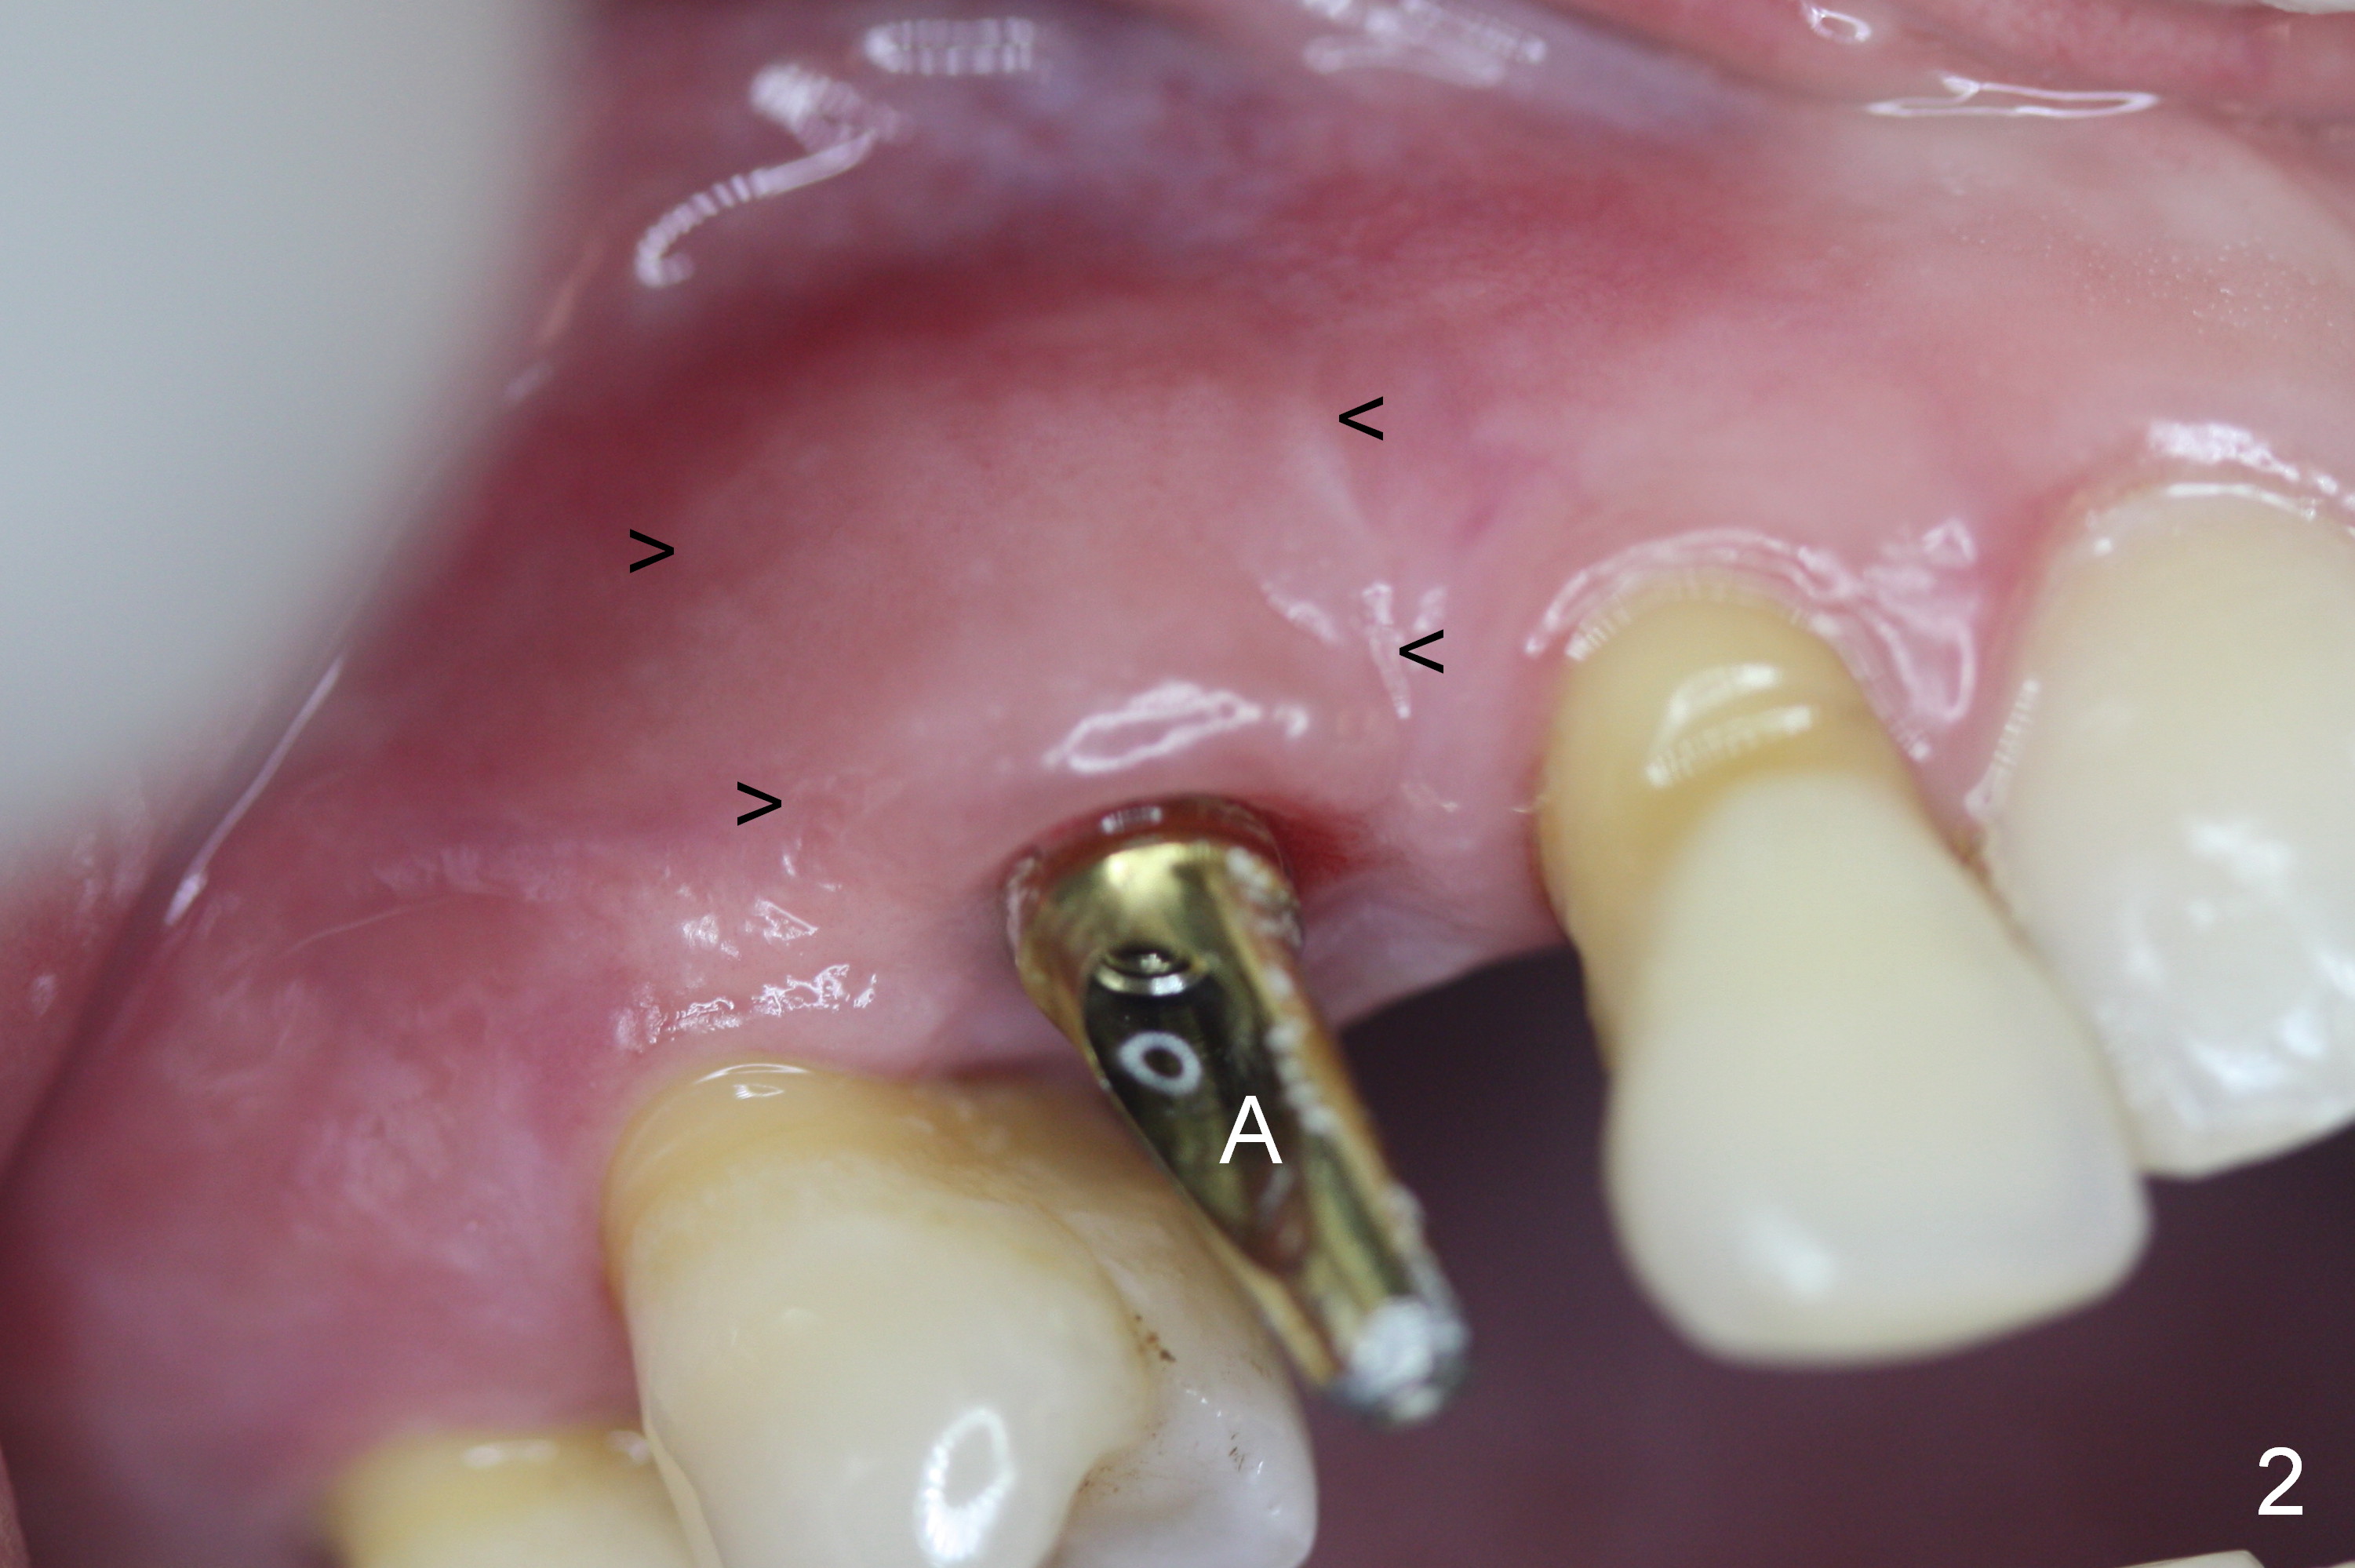

Four months post implant placement, the immediate provisional (Fig.1 P) has mobility with tenderness and perforation at the cervix (^). When the provisional is removed, the buccal plate bulging is more evident (Fig.2 arrowheads). The latter is apparently caused by bone expansion associated with implant placement (Fig.3 black *), since the bulging is not so obvious in a preop CBCT 3 D image (Fig.4 *). There is a layer of fiber granulation tissue (Fig.3 white *) around the mobile implant (I). More fiber tissue is noted when the implant is removed (Fig.5). A new osteotomy is created in the palatal wall of the existing implant site with 2 mm pilot drill, followed by 2.5 and 3 mm reamers. As a 4.5x17 mm tap is being inserted (Fig.6 T), it is deviated buccally. Reamers are re-used to try to remove more palatal bone to let the implant be placed more palatally. When a 4.5x17 mm tissue-level implant is placed (Fig.7,8 I with insertion torque >60 Ncm), there is a small buccal gap (Fig.8 *). A 20° angled abutment (Fig.7,8 A) is placed. An immediate provisional is fabricated with cosmetic satisfaction.